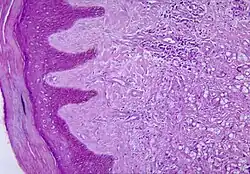

Histopathological changes in the skin seen in lobomycosis. Source: CDC

Diagnosis of Lobo's disease is made by taking a sample of the infected skin (a skin biopsy) and examining it under the microscope. Lacazia loboi is characterized by long chains of spherical cells interconnected by tubules. The cells appear to be yeast-like with a diameter of 5 to 12 μm. Attempts to culture L. loboi have so far been unsuccessful.[10]